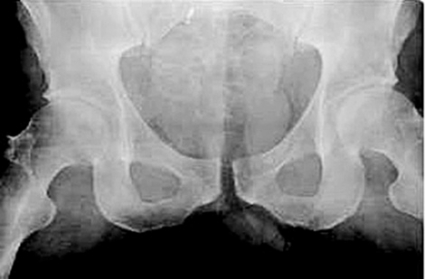

• Anteroposteriort genom direkt våld mot bakre spina alternativt os pubis eller genom utåtrotationsvåld via ena eller båda höftlederna, ledande till utåtrotation av bäckenhalvorna, »open book«-skada. Detta ses hos t ex förare av bil vid frontalkollision, hos fotgängare påkörd av bil, vid MC-olycka eller vid ridolycka då ryttare faller baklänges med hästen över sig (Figur 4, överst).